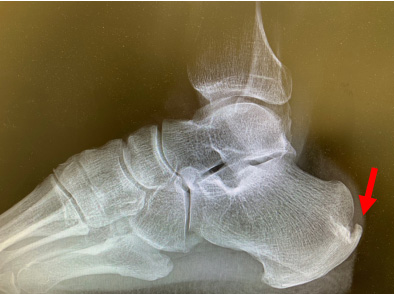

● X光片可以看到跟腱止点区域骨质增生,跟腱内钙化;